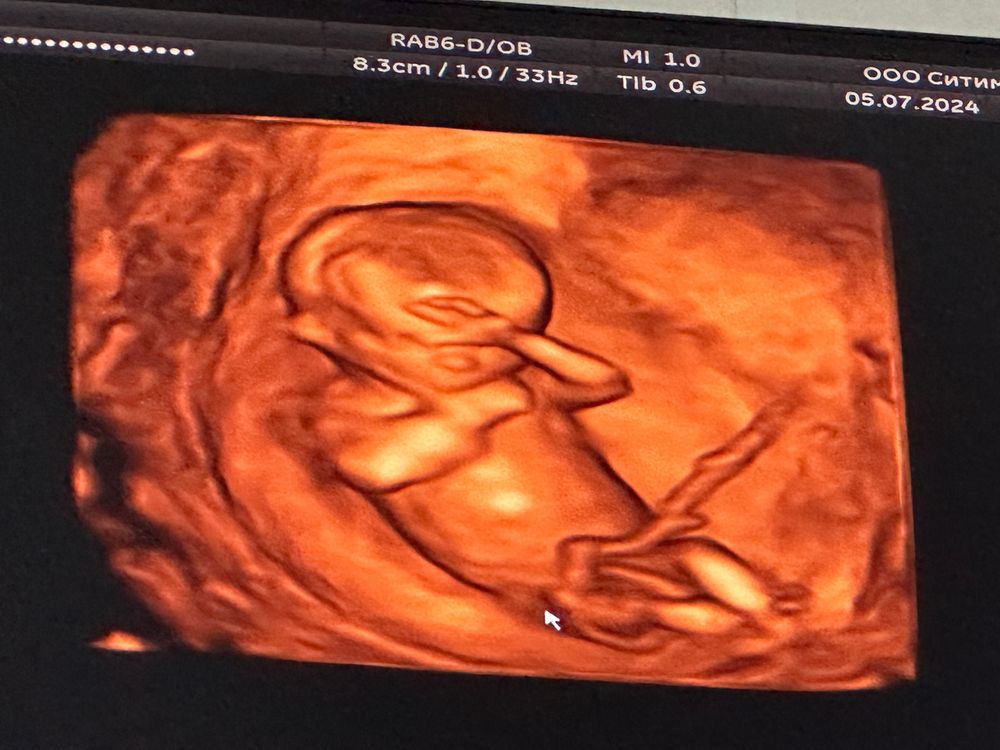

Оля в Благополучная беременность год 13/5 Нед узи УЗИ, КТГ, доплер Посмотрите еще 20 записей на эту тему Отменить Ответить Anastasiya Какой уже карапузик ❤️❤️❤️, как быстро летит время... 07.07.2024 Ответить Оля Anastasiya, по мне дык медленно :)))) но хотя бы 1 триместр пройден уже достижение 07.07.2024 Ответить Anastasiya Оля, впереди всё самое интересное😊😊😊 08.07.2024 Ответить Высокая чсс на 12 неделях, тахикардия плода Допплер фетальный Чаты Беременных Выберите чат: Январята-2026 Февралята-2026 Мартята-2026 Апрелята-2026 Майчата-2026 Июнята-2026 Июлята-2026 Августята-2026